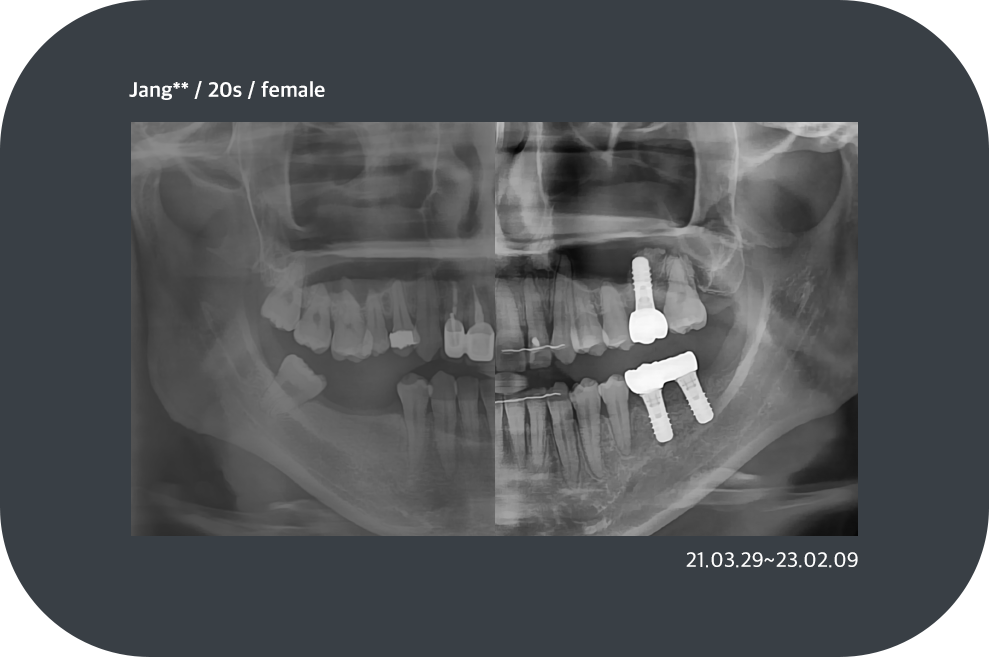

치료사례

임플란트 치료사례

*모든 증례 사진은 의료법 제23조, 제56조에 의거하여, 당사자의 동의하에 게시하였습니다.

*치료 사진은 모두 본원에서 치료한 환자분의 사진입니다.

*치료 사진은 모두 동일인의 사진이며, 동일조건에서 촬영하였습니다.

*개인의 차이에 따라 시술 및 수술 후 부작용이 발생할 수 있으며, 의료진과 충분한 상담을 받으시기 바랍니다.